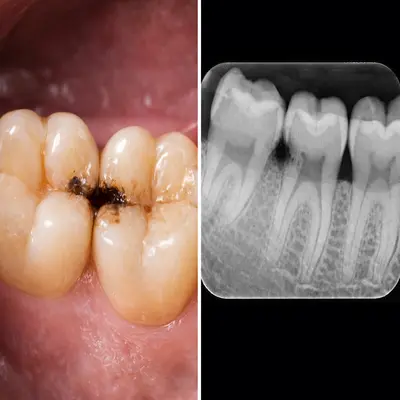

جراحی دندان عقل نهفته با دریل جراحی و نمای واقعی از استخوان فک

دندان عقل در انتهای دهان قرار دارد و بهخوبی تمیز نمیشود؛ همین موضوع احتمال گیر غذایی، التهاب لثه و عفونتهای مکرر را بالا میبرد. عفونتهای تکرارشونده میتوانند به دردهای مداوم و حتی دردهای مزمن فک منجر شوند.

با گذشت زمان، فشار دندان عقل به دندانهای کناری میتواند باعث آسیب به دندان مجاور، پوسیدگی بیندندانی یا تحلیل استخوان موضعی شود؛ مشکلاتی که درمان آنها ساده نیست.